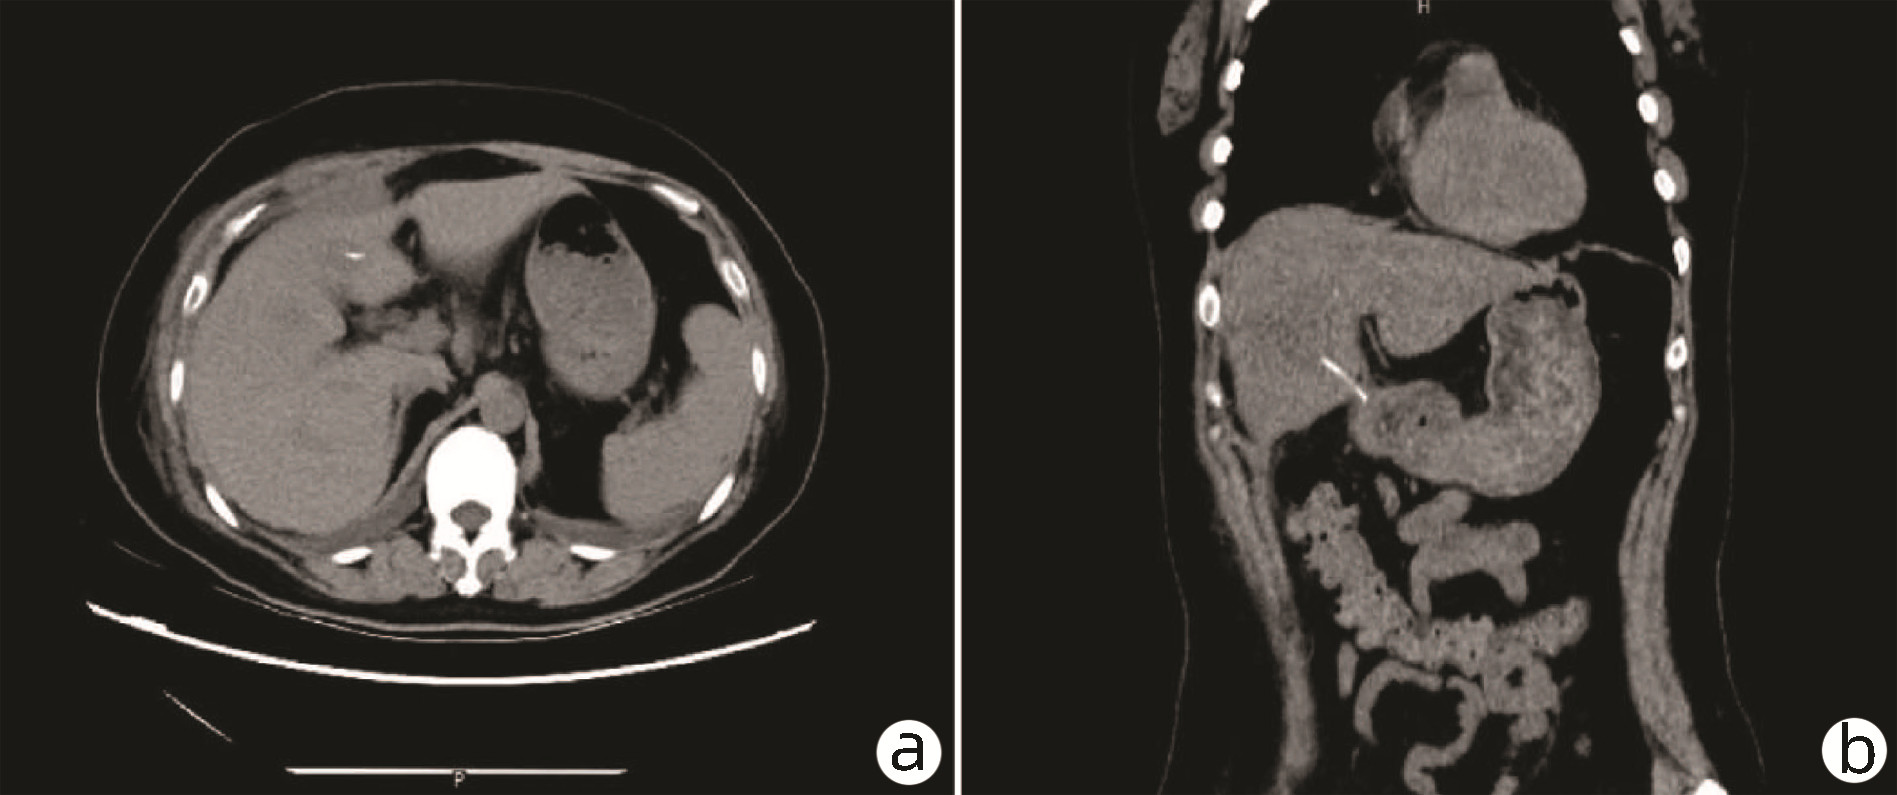

Endoscopic sequential ligation for treatment of esophageal and gastric varices with duodenal varices: A case report

Hao WEN, Zhaohui HE, Tong JIANG, Guoqing SHI

2023, 39(3): 637-639. DOI: 10.3969/j.issn.1001-5256.2023.03.024

Abstract(837) HTML (263) PDF (2676KB)(95)

Abstract: